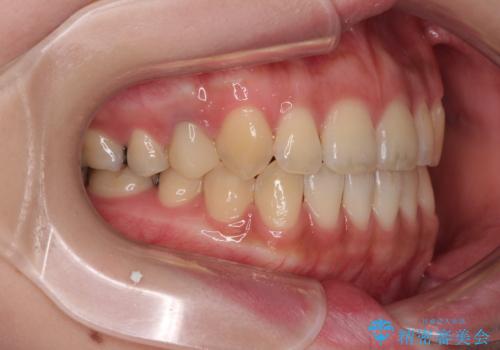

開咬をワイヤー装置で矯正治療

- 上下前歯が非接触となっている咬み合わせを気にして来院された患者様です。

開咬となっている原因の大半は、舌の突出癖によるものであるため、治療開始前から舌のトレーニングを開始し、スムーズに治療が進むようにしました。

治療開始から8ヶ月ほどで遠方への転勤が決まりましたが、歯列は概ね整っていたため、その後は東京出張を狙って治療を終える処置を行うことができました。